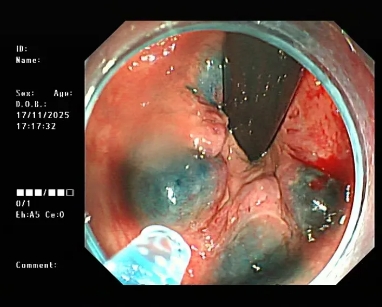

图片

△内镜下硬化治疗